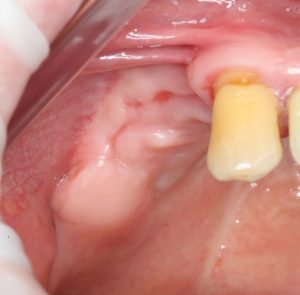

Или другой вариант. Не было условий для нормальной имплантации и протезирования:

Потом бах! И эти условия появились:

По сути, «костная ткань выросла»! Чудо? Очень похоже на чудо. На деле, простое понимание регенеративных процессов в костной ткани и немного правильного мануала:

и у нас теперь есть условия для имплантологического лечения и вменяемого протезирования отсутствующих зубов.